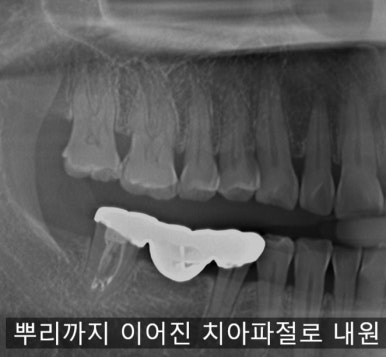

1️⃣ 즉시 식립(Immediate Implant)

즉시 식립은 이름 그대로

치아를 뽑은 당일, 같은 자리에서 임플란트를 심는 방법입니다.